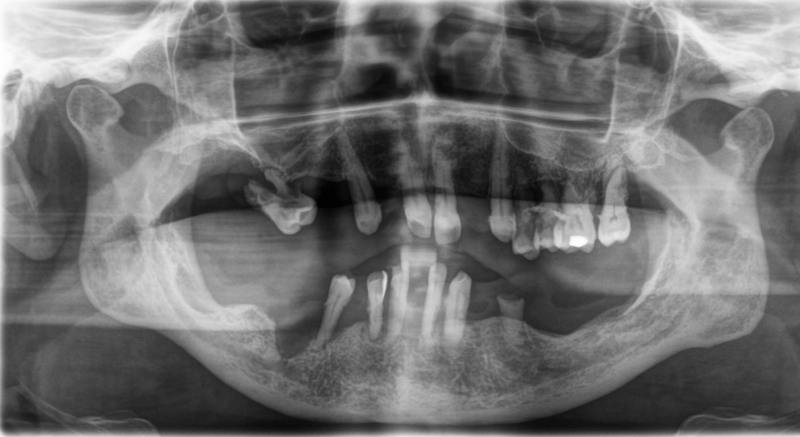

OPG nach Entfernung von Zahnstein, Gingivahyperplasien und Prothesen (inklusive Zahn 47 ).